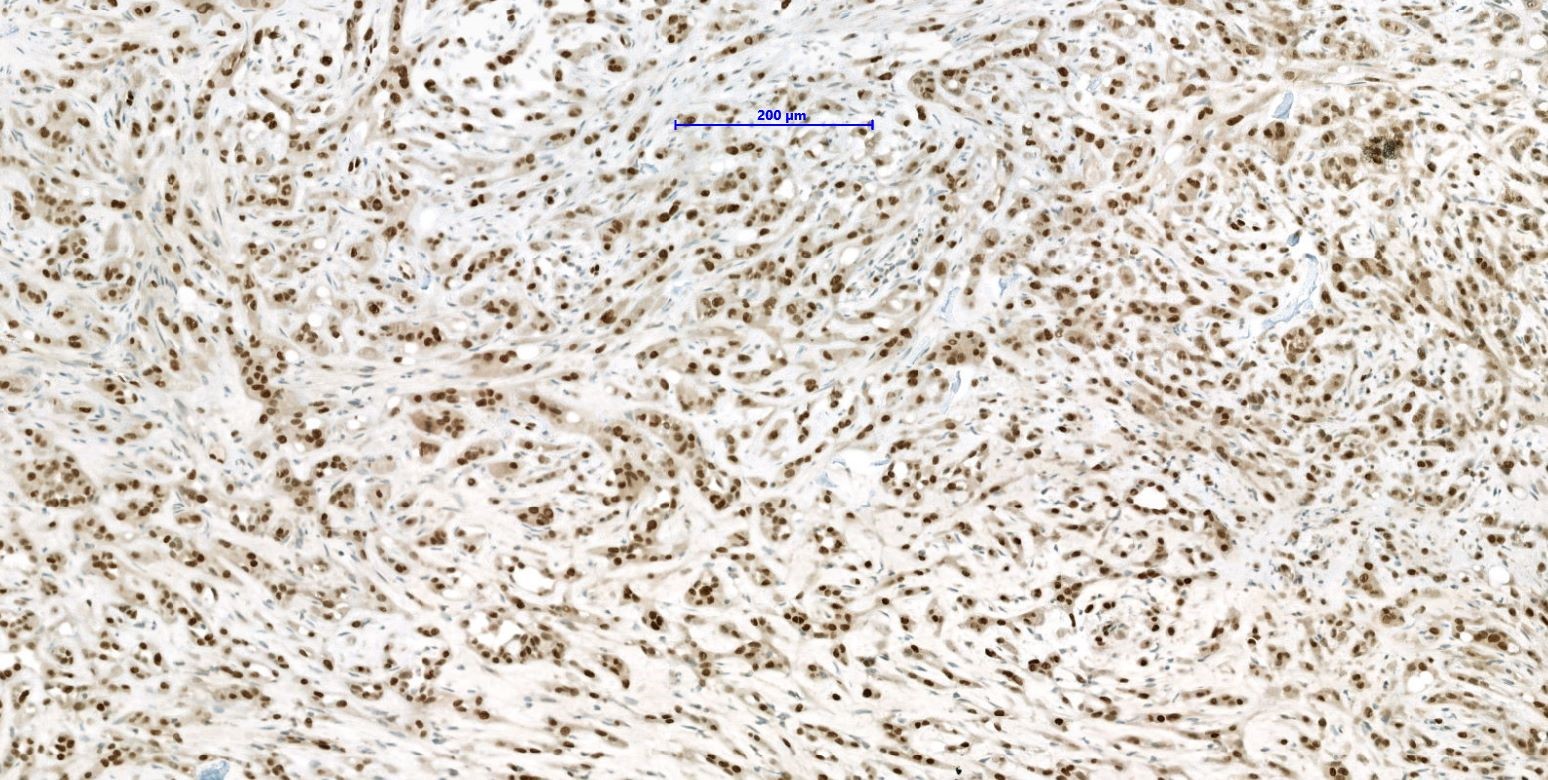

Microscopic (histologic) images

- YAP-TFE3 subtype:

- Solid nests or pseudo alveolar arrangement of epithelioid cells enmeshed in a fibrous stroma

- Tumor cells have abundant, densely eosinophilic cytoplasm and can form vascular spaces

- Intracytoplasmic vacuoles are rare

- Usually minimal mitotic activity, atypia or necrosis

- TFE3 in YAP-TFE3 rearranged (less specific) (Genes Chromosomes Cancer 2013;52:775)

- YAP1-TFE3 rearranged tumors: composed of solid nests or pseudo alveolar formations of epithelioid cells enmeshed in a fibrous stroma; TFE3 positive staining